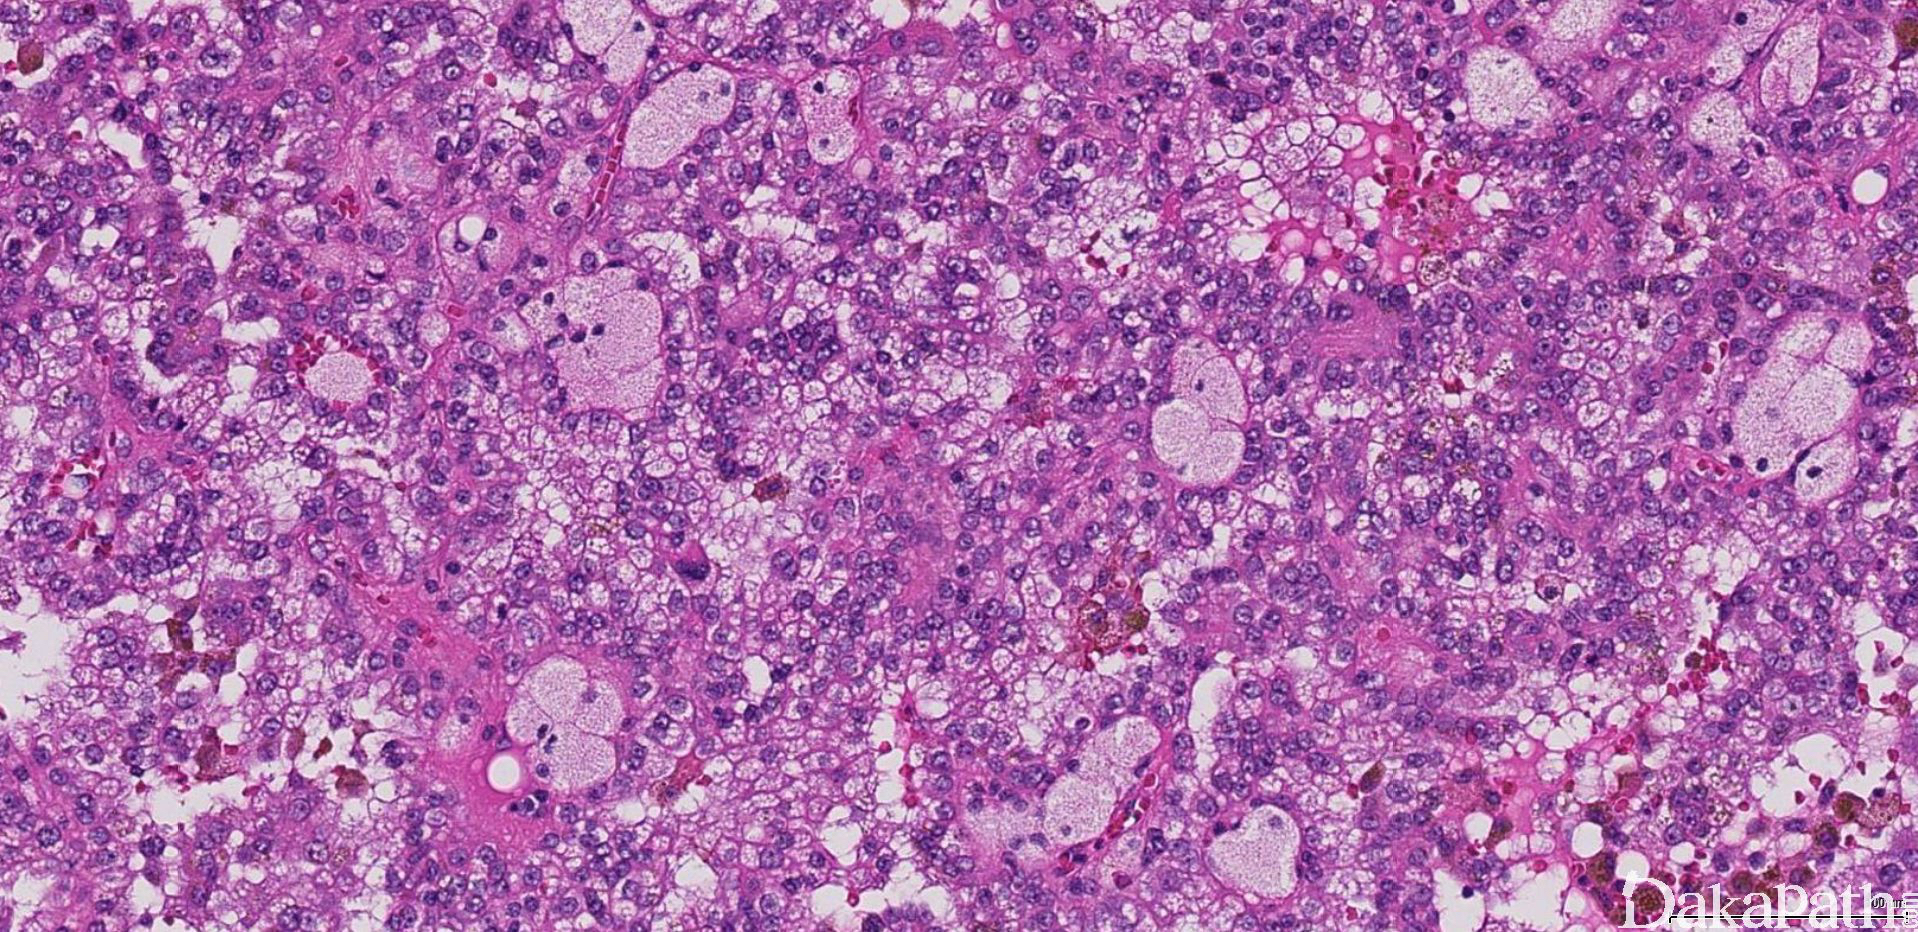

镜下可见由具纤细的纤维血管轴心的乳头状结构及管状结构构成,纤维血管轴心可有泡沫状巨噬细胞、胆固醇结晶和砂粒体,偶尔纤维血管轴心因水肿或玻璃样变纤维组织而增宽;

部分可见肾小球样结构、微结节类似于顿挫的乳头状结构,部分病例以管状结构为主,或乳头拥挤似实性结构;

常见出血和坏死,巨噬细胞内、间质和肿瘤细胞浆内可有含铁血黄素;

1 型:乳头表面被覆小的立方状细胞,胞浆稀少嗜碱性,部分可表现为透明胞浆,单层排列,该型者多灶性病变常见;

2 型:被覆瘤细胞呈假复层排列,胞浆丰富嗜酸性,核级别高可见明显的核仁;部分肿瘤具有丰富的分布均匀的细颗粒状嗜酸性胞浆,核低级别,呈单层线性朝向乳头表面或管状结构的腔面分布,呈嗜酸细胞瘤样,又称为嗜酸细胞性乳头状癌;局部可见明显的淋巴样间质浸润,组织学类似于 Warthin 瘤,又称为 Warthin 瘤样乳头状肾细胞癌;